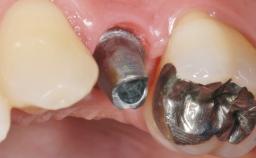

A 56-year-old female patient was referred to the clinic for the functional rehabilitation of her left mandible. The healthy, non-smoking patient presented with loss of retention of crown 35 due to secondary root caries. In addition, she had a single-tooth gap at site 36 with clearly discernible facial atrophy. The panoramic radiograph exhibited crowned teeth 35 and 37, both with a root canal filling. Tooth 37 showed a radiolucent area on the mesial aspect. Tooth 38 did not show any signs of pathology. Based on the clinical and radiographic findings, it was decided to remove root 35 and tooth 37, creating an extended edentulous space with three missing teeth. As requested by the patient, tooth 38 was left in place. The removal of both teeth was done without major flap elevation. The wound margins at site 35 had to be slightly elevated to remove the root remnant.